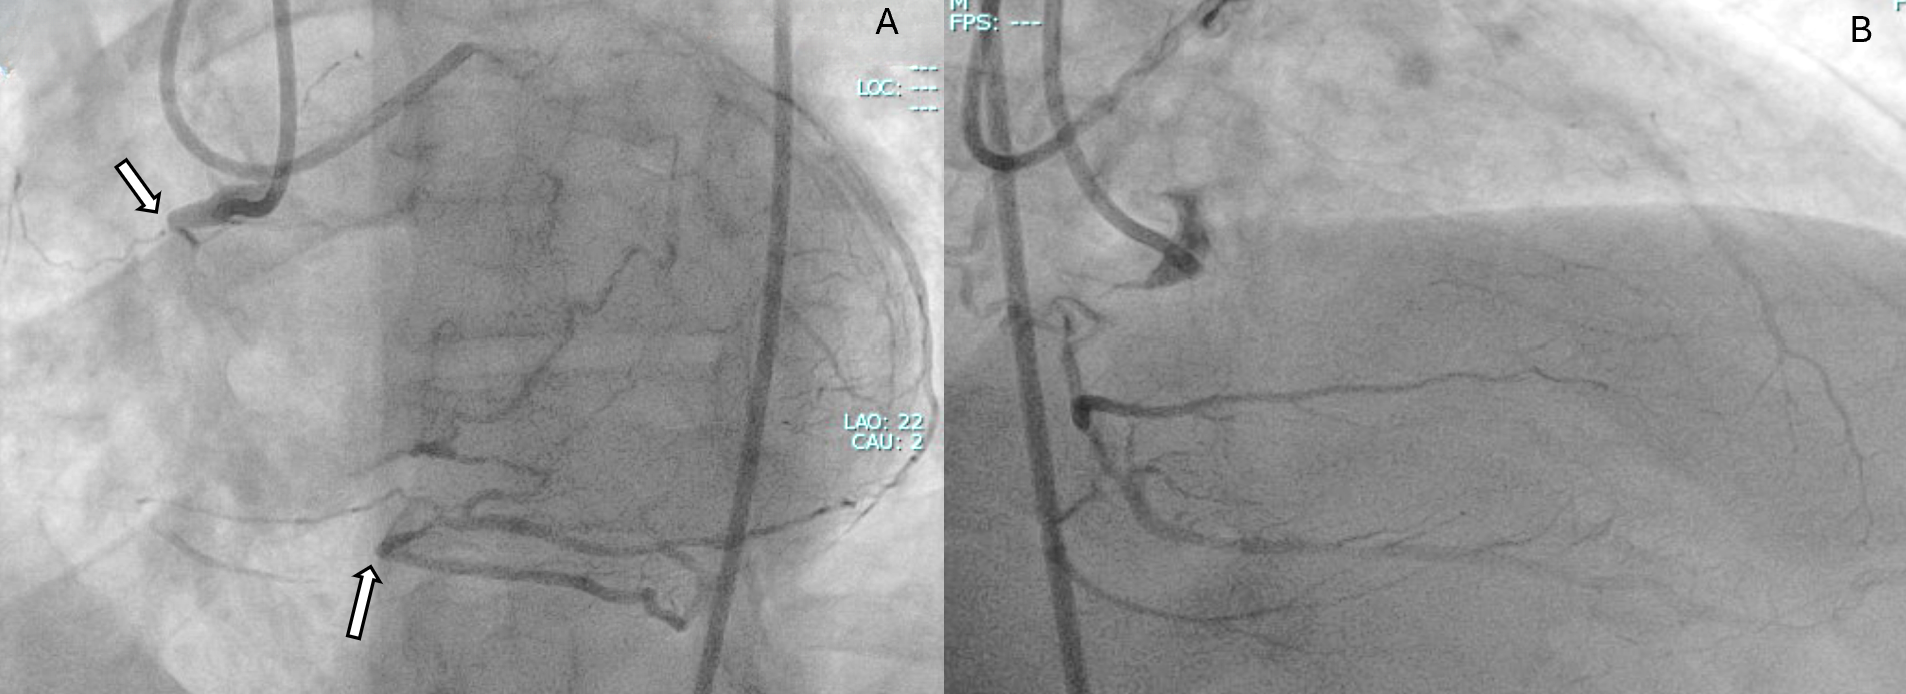

A 59-year-old man with exertional angina and coronary angiography showing chronic total occlusion (CTO) of the right coronary artery (RCA) with collateral filling from the left anterior descending artery (LAD) (Figure 1). Dual injection revealed an ambiguous proximal cap, a very long occlusion, and the distal cap at the bifurcation (Video 1).

A primary retrograde strategy was selected but septal collateral wiring was unsuccessful. Epicardial collaterals from the LAD were subsequently crossed (Figure 2, Video 2); however, a retrograde wire (Confianza Pro 12; ASAHI INTECC) failed to puncture the distal cap. Antegrade wire (Gladius MG; ASAHI INTEC) knuckle was used until just before it reached the distal cap (Figure 3, Videos 3 and 4). A 3.0 x 20-mm TREK balloon (Abbott) was delivered retrogradely through the epicardial collateral and inflated at the bifurcation (Video 5). Next, an antegrade wire (Gladius EX; ASAHI INTECC) was delivered into the distal true lumen of the posterior descending artery (Figure 4, Video 6). The RCA was successfully stented with an XIENCE Pro drug-eluting stent (Abbott), with restoration of Thrombolysis in Myocardial Infarction 3 flow (Figure 5, Video 7).